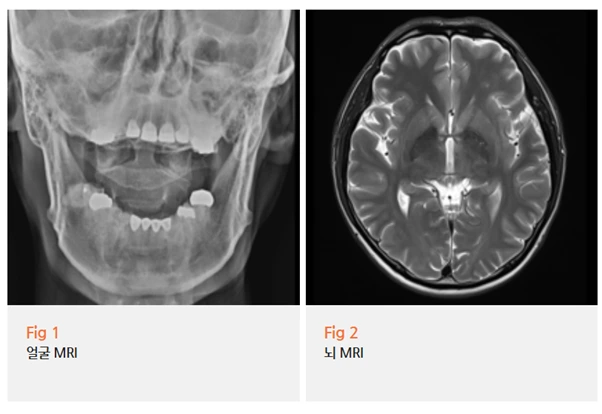

저는 이분께 먼저 당일 뇌 MRI 검사를 권했어요.

3차신경통 병원에서 왜 뇌 검사를 하냐고 의아하게 생각하실 수도 있는데요.

사실 이 결정이 굉장히 중요합니다.

삼차신경통과 비슷한 증상을 보이는 경우 중에는

뇌종양, 혈관 기형, 다발성 경화증처럼 구조적 이상이 원인인 경우도 있거든요.

이걸 확인하지 않고 단순 신경통으로 처리하면 안 되는 이유가 여기에 있어요.

증상이 신경통처럼 보인다고 해서 신경통이라고 바로 결론 내리는 건 위험할 수 있습니다.

다행히 이분의 경우, MRI에서 뇌 병변은 확인되지 않았어요.

기질적 이상이 없다는 게 확인된 이후,

저는 임상 양상을 종합해서 삼차신경통 의증으로 판단했습니다.